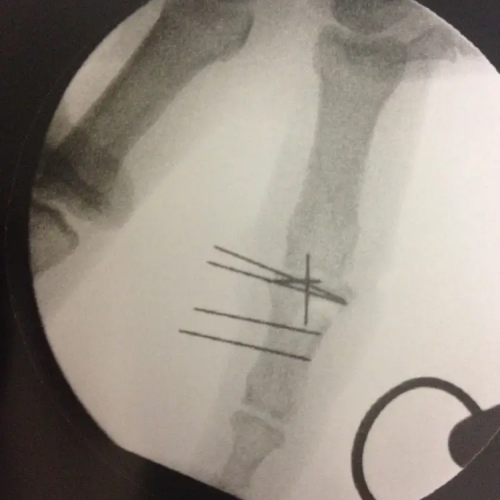

- fractures